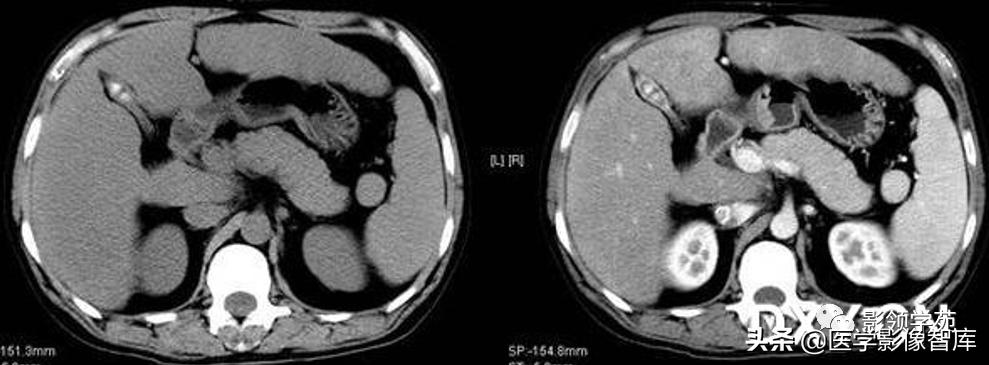

1.CT平扫:1)脾内见圆形、类圆形低密度病灶,边界较清楚。2)较大血管瘤时,脾脏体积可增大,瘤体中央可有瘢痕形成,表现为更低密度,当内部有新鲜出血时,可见高密度区。3)病灶大小不等,多为单发,也可多发,可见有斑点状、星芒状钙化灶。

2.增强扫描:1)肿瘤边缘多呈斑片状强化,静脉期和平衡期强化扩大并逐渐向中心充填,延迟后与正常脾脏密度一致。与肝血管瘤呈类似改变。2)当肿瘤中心有血栓形成或瘢痕存在时,中心可有始终不强化区域。